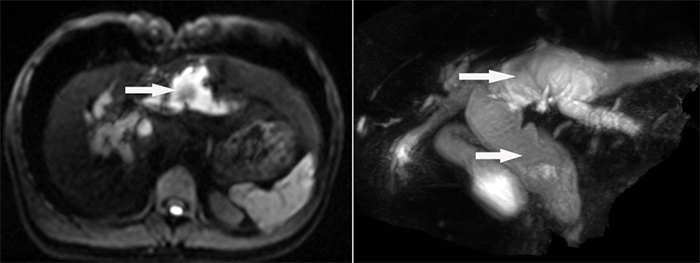

腹部增強(qiáng)CT顯示肝內(nèi)外膽管囊狀病變

為盡快解除病痛,早日回歸正常生活,主管醫(yī)生與患者及患者家屬就該疾病進(jìn)行了詳細(xì)溝通和交流,進(jìn)行了腹部增強(qiáng)CT、MRCP等相關(guān)檢查,明確了病因和疾病位置,患者診斷為先天性膽管擴(kuò)張癥(Ⅳ型)、肝內(nèi)外膽管結(jié)石,并進(jìn)行了住院治療。

MRCP顯示肝內(nèi)外膽管囊狀病變及膽管結(jié)石

經(jīng)科室內(nèi)全體醫(yī)生討論,先天性膽管擴(kuò)張癥的并發(fā)癥發(fā)生率高達(dá)20~60%,且有一定癌變率,癌變率隨患者年齡增大而遞增。該患者病變廣泛并波及肝內(nèi)外膽管,除肝外膽管顯著囊狀擴(kuò)張外,肝內(nèi)膽管囊狀擴(kuò)張以左半肝內(nèi)膽管顯著并膽管結(jié)石,患者手術(shù)指針明確。